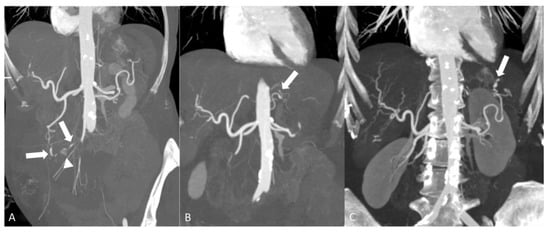

2.2. Medium-Vessel Vasculitis

2.2.1. Polyarteritis Nodosa

- Singhal, M.; Gupta, P.; Sharma, A.; Lal, A.; Rathi, M.; Khandelwal, N. Role of multidetector abdominal CT in the evaluation of abnormalities in polyarteritis nodosa. Clin. Radiol. 2016, 71, 222–227. [Google Scholar] [CrossRef] [PubMed]

- Chen, Z.; Zhao, Y.; Wang, Q.; Li, Y.; Li, H.; Zhou, Y. Imaging features of 18F-FDG PET/CT in different types of systemic vasculitis. Clin. Rheumatol. 2022, 41, 1499–1509. [Google Scholar] [CrossRef] [PubMed]